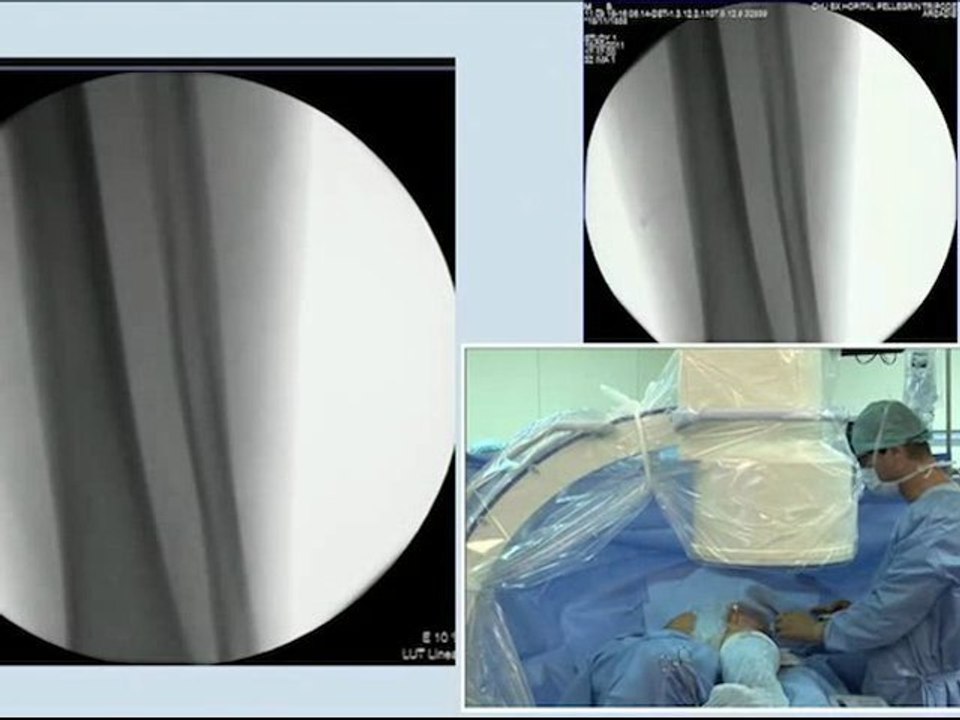

15 combined disease coronary artery stenting and left carotid artery stenting incathlab.com